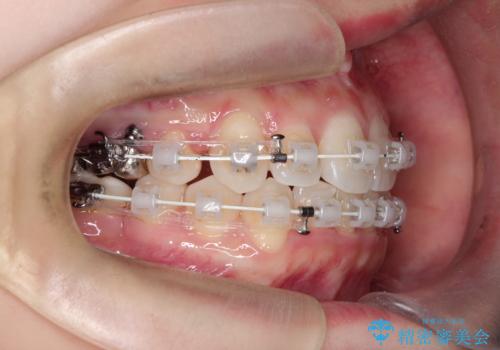

ワイヤー矯正を用いて、欠損部の閉鎖を目的とした後方からの歯の挺出・移動を行いました。

特に、親知らずを活用し、奥歯の噛み合わせを構築することに重点を置きました。